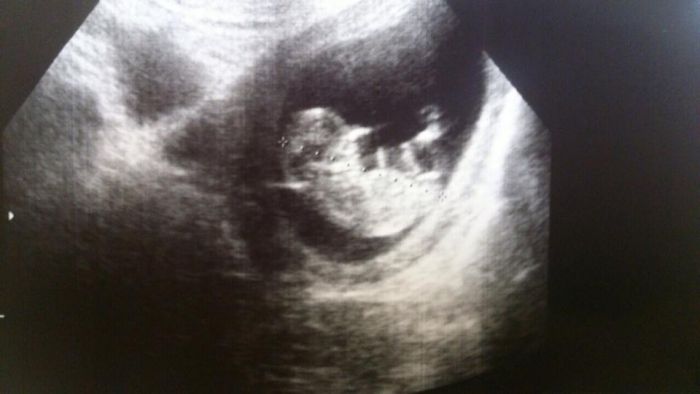

Ahojte devcata,tak uz mame kontrolu za sebou, po puldennim sezeni v nemocnici jsme tu nasi fazolku videli, pripadalo me to,ze chrnela, hybala jenom trosicku rucickama,tak me segra na priste poradila at se pred scanem napiju studene vody,ze to prcky probere, ale zase mozna bude horsi je zmerit xixi uz mame 4,7cm a jsem pry podle velikosti 11+5tt, tak me potvrdili TP 1.6.14 takze poncialne na den deti bude mim naseho prvniho potomka, jinak 25.11 jsem objednana do olomouce na 11tt-13tt kontrolu, jelikoz se tady plati vysetreni na downuv syntrom,tak jsem se rozhodla,ze pojedu na par dni domu, jelikoz se uz v lete domu nedostanu,tak spojim prijemne s uzitecnym, aspon sebou muzu vzit nastavajici babicku at se podiva na naseho prcka.